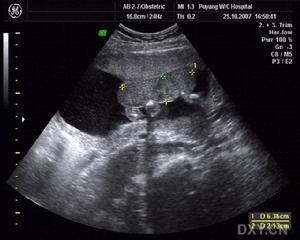

確定頭小畸形是要以頭圓周,即前額腦區底部圓周,來與適當的生長表作出比較。其他結構性缺憾可以透過成像技術來觀察。由於成像過程昂貴及相對地較難接近,胎兒酒精綜合症很少會以非頭小畸形的結構性缺憾來診斷。